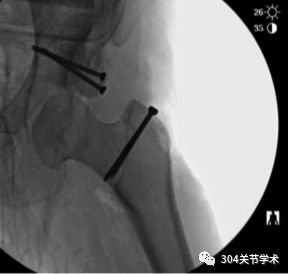

关节囊成形术为年轻发育性髋关节脱位患者的保髋治疗方法之一,若适应证选择合适,该手术方式或可对股骨头软骨正常的髋脱位患者提供有效的保髋机会。本文描述了1例27岁女性发育性髋关节脱位患者,总结了结合髋关节外科脱位行关节囊成形术的治疗经验。正常情况下,该手术是经髋臼缘游离关节囊后,将关节囊完整包裹股骨头后,复位股骨头至磨锉后的髋臼中,以在股骨头软骨与关节囊之间形成新的关节界面。而本文这例患者,术中由于关节囊不足以包裹股骨头,故选用40mm*70mm大小、厚度3mm的脱细胞真皮同种异体移植物代替关节囊附于髋臼内,并复位股骨头后,将移植物周缘与患者自身关节囊修补缝合。复位股骨头的方法采用“降落伞”法,即将移植物4个角分别缝合牵拉,形如降落伞(图),将其贴附于磨锉后的髋臼后,维持4个角的牵拉力,保持移植物位置不变,轻柔复位股骨头。术后支具维持髋关节外展位3月,并逐渐调整减小外展角度。3月后逐渐开始负重并增加关节活动度。该患者截止术后8月,股骨头位置良好,髋关节活动度为屈髋100度,后伸10度,行走不需要支具且无跛行。

脱细胞真皮同种异体移植物

术前

术中

术后即刻,外展支具固定

术后8个月